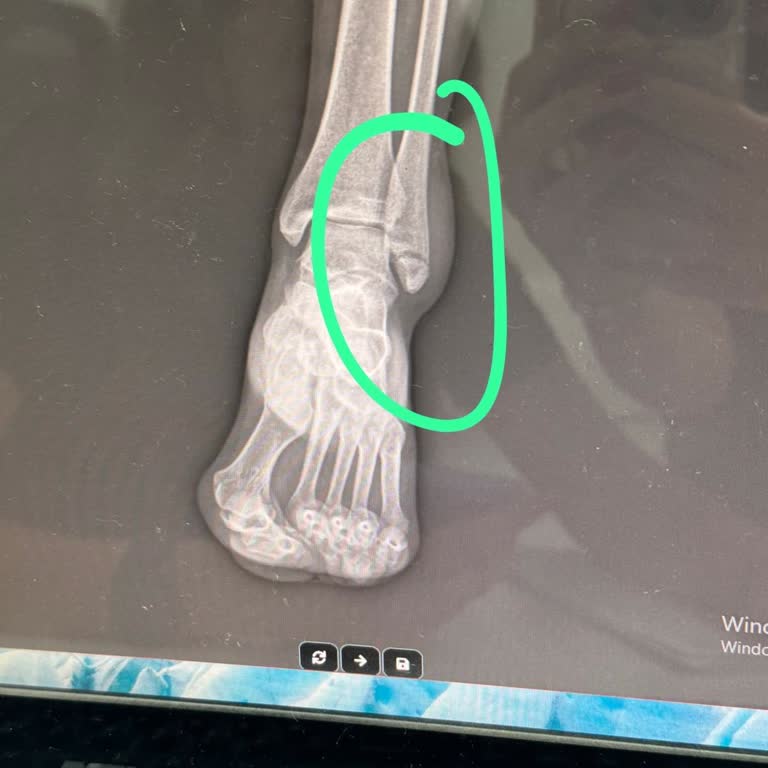

ameliyat